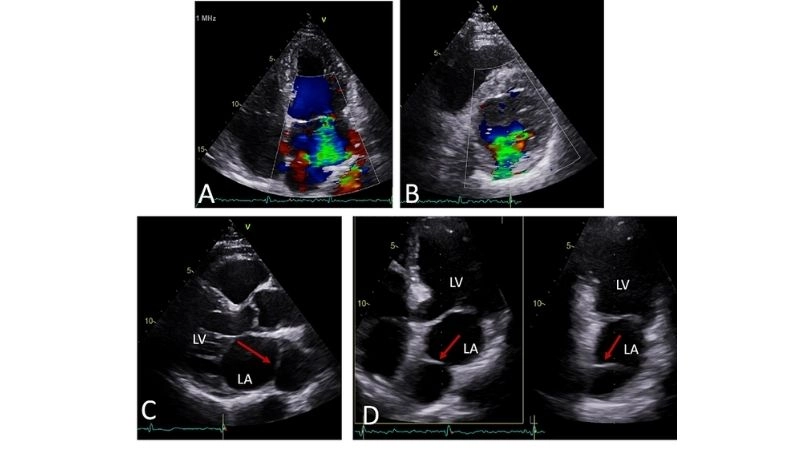

Images visual examples of cor triatriatum

Visual examples of Cor Triatriatum often show the atrium divided by a thin membrane, creating two chambers that disrupt normal blood flow within the heart.